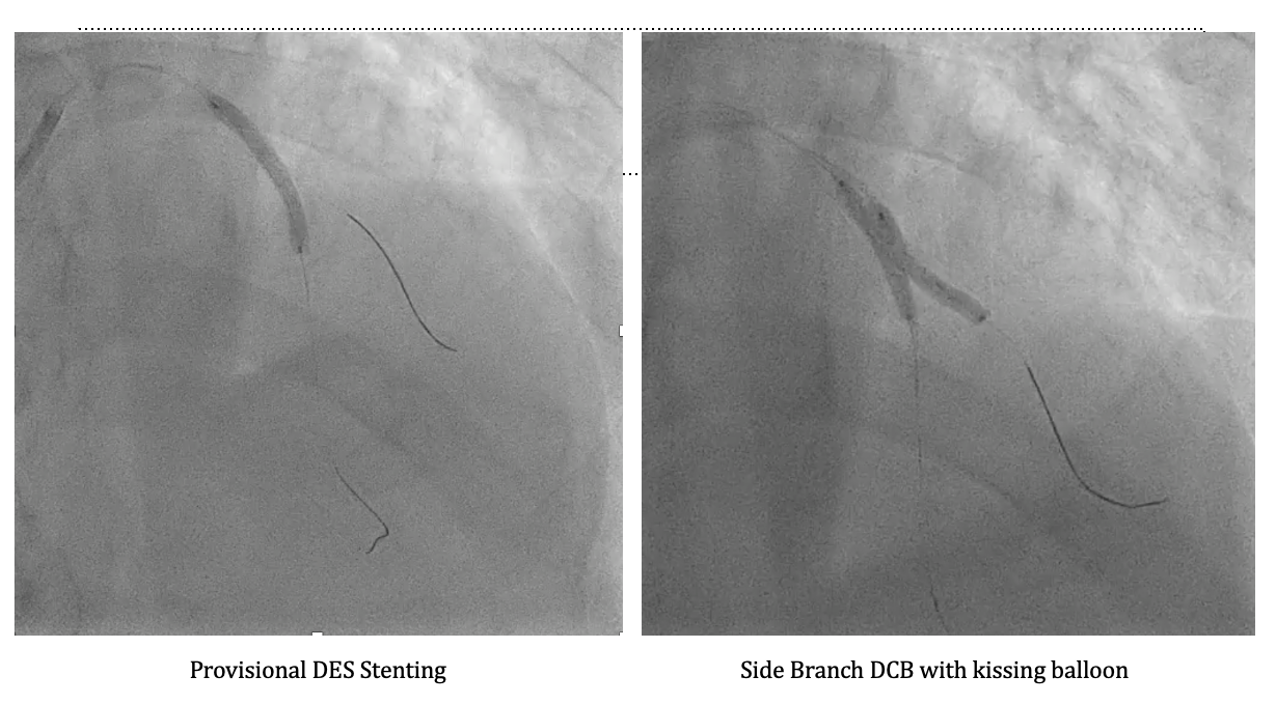

PCI was performed using a 6-in-7 Fr sheath through left radial access. Two wires were advanced (Pilot 50 to LAD-D and Terumo Floppy to LAD-D2), followed by predilatation of the LAD-M lesion with a 2.0¡¿20 mm balloon. OCT of LAD-M demonstrated a mixed fibroatheroma with superficial calcification <90¡Æ, some 90–180¡Æ beyond the LAD-D2 bifurcation, and a lipid pool proximal to the bifurcation, with calcification on the same side of the D2 ostium, guiding reference sizing to 3.0 mm distally and 4.25 mm proximally. OCT of LAD-D2 showed mixed fibroatheroma with ~90¡Æ superficial calcium and distal reference ~3.0 mm. Kissing balloon predilatation was performed, followed by Onyx Frontier 3.0¡¿26 mm DES deployment in LAD-M and POT with a 4.0¡¿12 mm NC balloon. Distal rewiring was performed, and incomplete distal stent expansion was corrected with a 3.0¡¿20 mm NC balloon. The side branch cell was opened using kissing balloon inflation. Post-stent RFR improved (LAD-D2: 0.73¡æ0.94; LAD-M: 0.80¡æ0.92), supporting DCB treatment for LAD-D2 with PREVAIL 3.0¡¿20 mm/10 ATM, followed by kissing balloon. OCT confirmed good apposition but underexpansion at LAD-M, which improved after further post-dilatation (MSA 3.53¡æ3.79 mm; expansion 65¡æ82%). Final POT was performed with a 4.0¡¿12 mm NC balloon. OCT of LAD-D2 showed a dissection to the media without flow limitation. The patient remained comfortable, and final physiology was good. The intended hybrid DCB side-branch treatment strategy was achieved.

This case illustrates that not every Medina 1.1.1 bifurcation lesion requires a two-stent strategy. OCT guided accurate lesion characterization and sizing for optimized main branch DES implantation, while RFR confirmed physiologic improvement and supported selective DCB treatment for the side branch. This hybrid approach preserved bifurcation geometry and avoided unnecessary metal. Moreover, this strategy aligns with the recent DCB Academic Research Consortium Position Statement, which endorses DCB use in appropriately selected bifurcation lesions following adequate lesion preparation and imaging guidance.